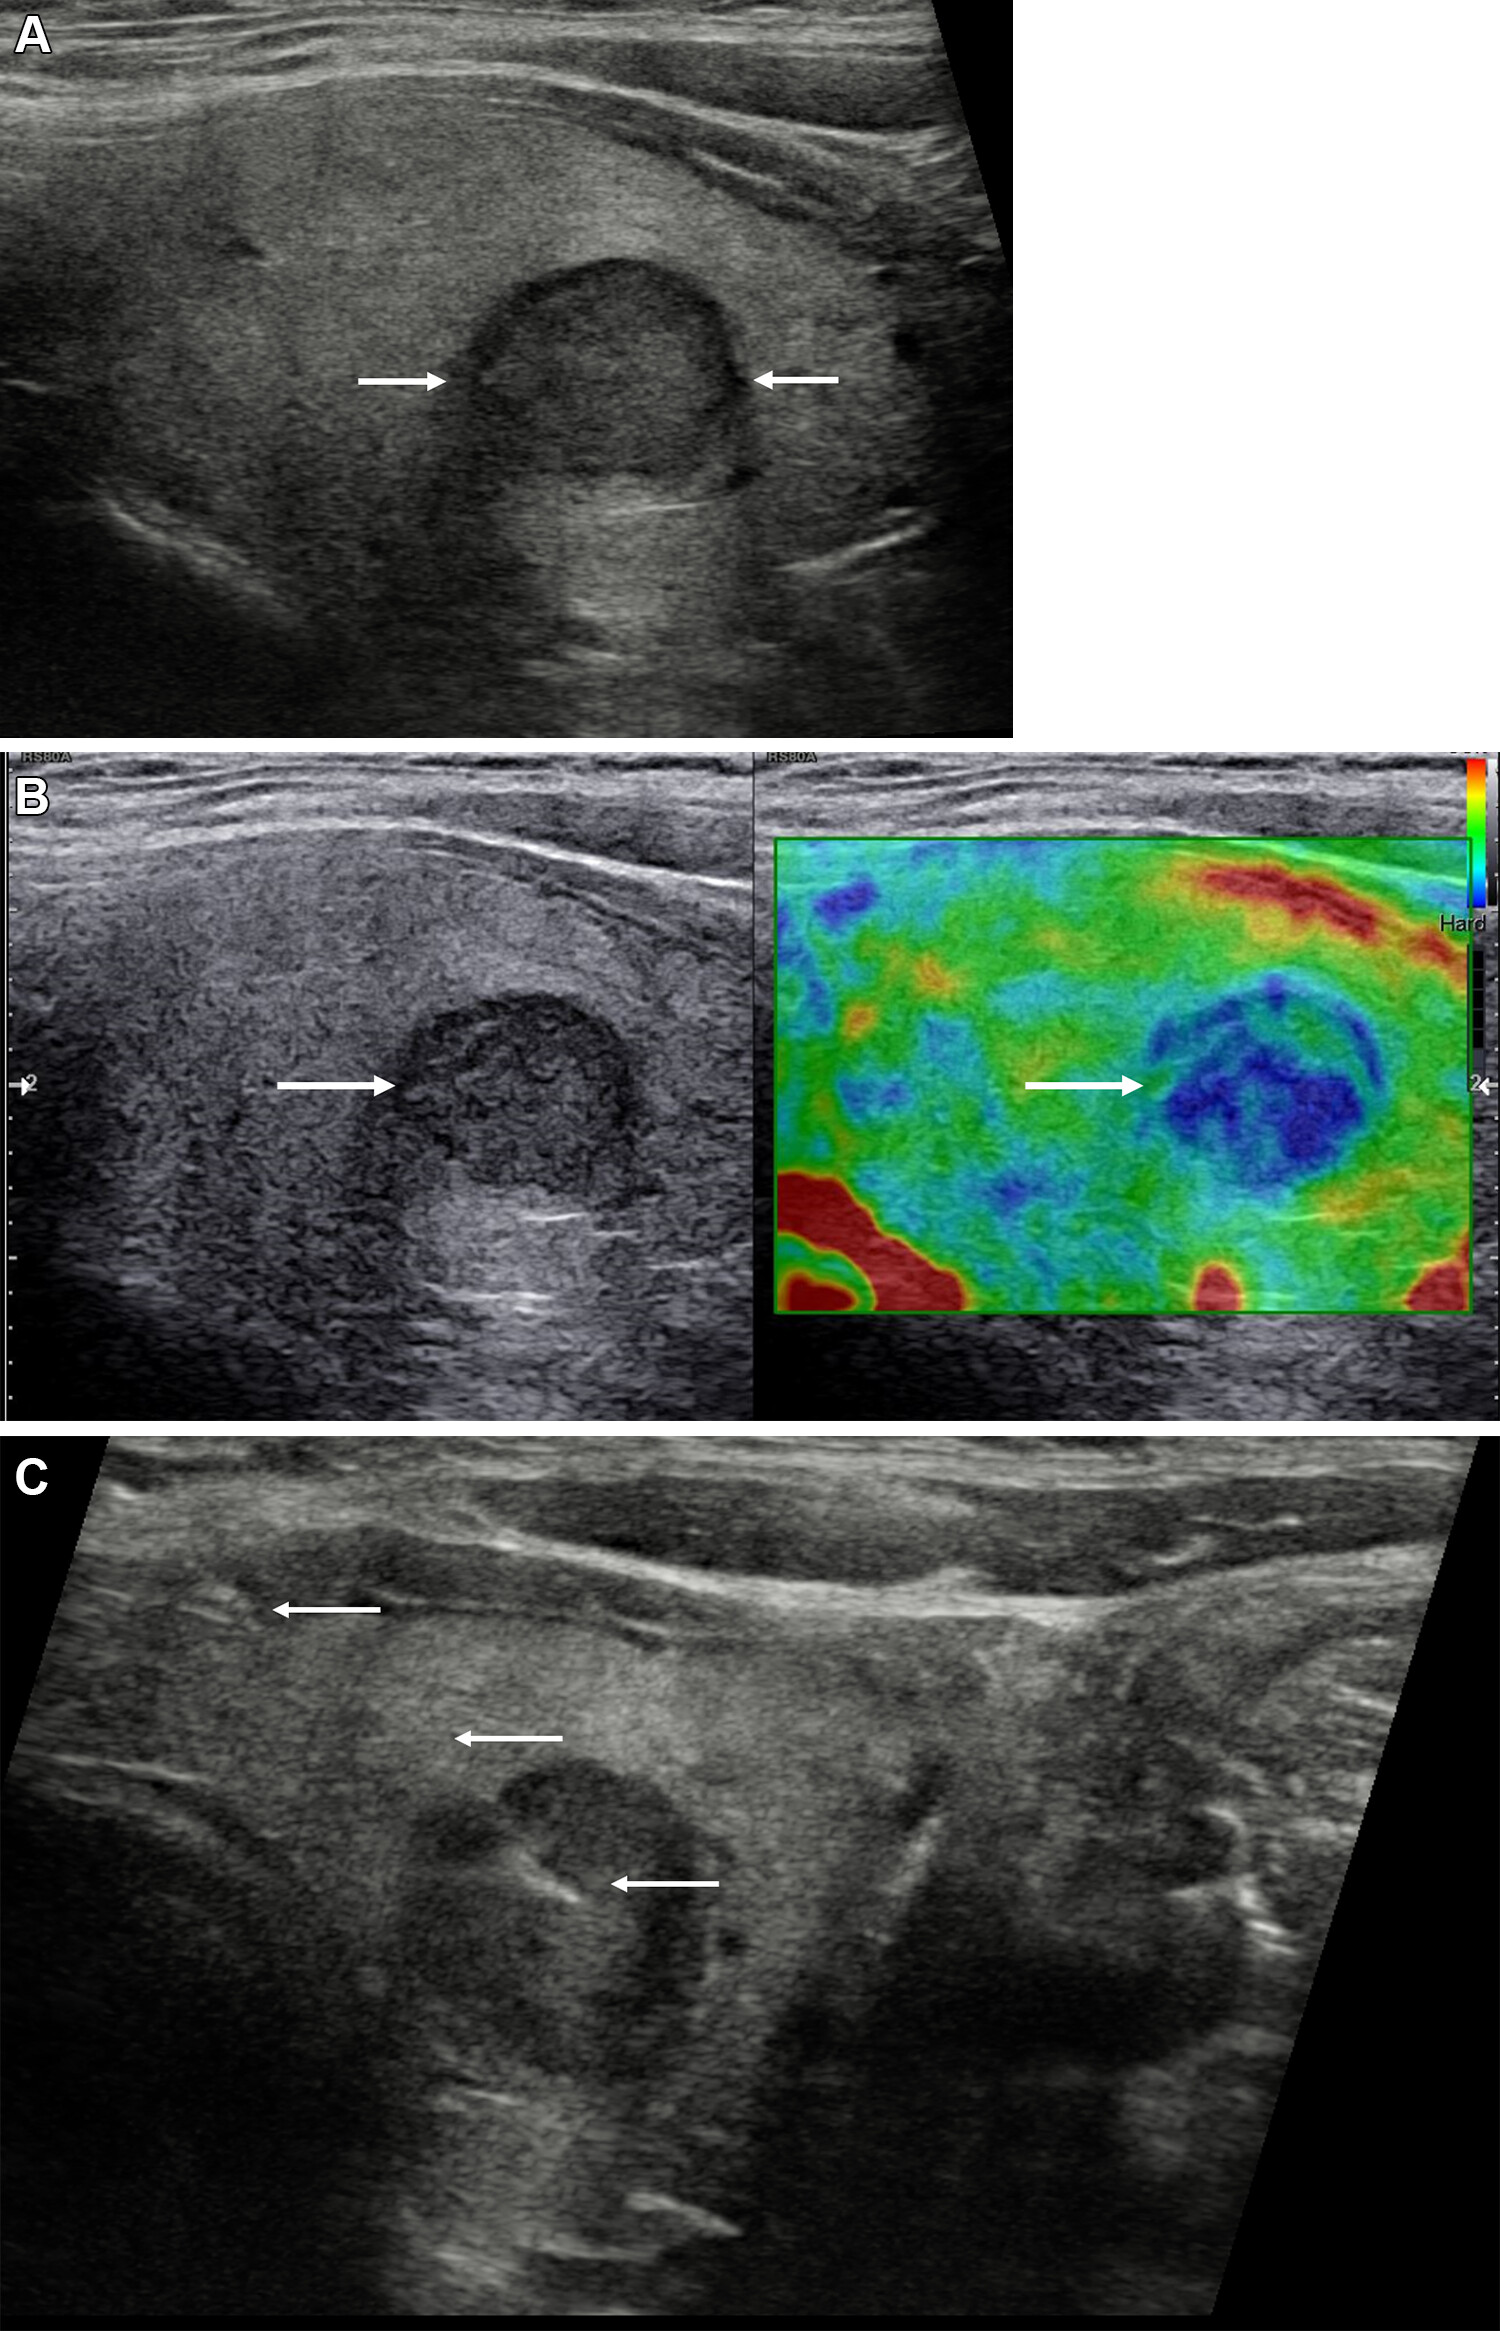

In an online poster presentation at the ARRS annual meeting, researchers led by Dr. Leila Aghaghazvini found that elastography and vascularity measures can help improve the performance of TI-RADS in assessing suspicious thyroid nodules. In these images, gray-scale features show a markedly hypoechoic thyroid nodule with irregular margins (TI-RADS 4), later confirmed as papillary thyroid cancer. (A) Elastography shows a mostly blue pattern. (B) Doppler sonography did not show any flow pattern. Images courtesy of the ARRS.The study included 200 total thyroid nodules, assessed by conventional sonography to gather TI-RADS scores and important characteristics. The investigators used a 7.5 MHz probe to assess vascularity pattern and resistive index, performed quantitative elastography evaluations via color mapping, and calculated average and maximum velocities. They confirmed final diagnoses of all thyroid nodules via histopathology assessment or follow-up imaging.